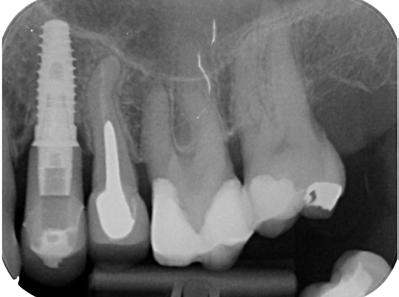

1. ábra: Kiindulási röntgen. A felső nagyőrlőfog trepanálását akut beavatkozásként egy másik rendelőben végezték.

2. ábra: A hozzáférési nyílás kialakítása során túlzott mértékű ép foganyag eltávolítása történt mesiobukkális és apikális irányba.

– 3. ábra: A visszamaradt nagy méretű pulpakő teljes mértékben elzárja a palatinális csatornabemenetet. – 4. ábra: A gyökértömés behelyezése előtt látható állapot. A csatornák feltágítása és tisztítása befejeződött.

5. ábra: Egyéves kontrollröntgen. – 6. ábra: Kiindulási felvétel. A mesiális irányba dőlt alsó első nagyőrlőfogat irreverzibilis pulpitissel diagnosztizáltuk, amely vélelmezhetően a disztális oldalán található parodontális lézióból indult ki. – 7. ábra: A posztoperatív felvételen látható, hogy a hozzáférési nyílás kialakítása a fog tengelyállásának megfelelő szögben történt.

8. ábra: A műtét előtti röntgenfelvétel a 45-ös és 46-os fogat érintő súlyos szuvasodási folyamatokat mutatja.